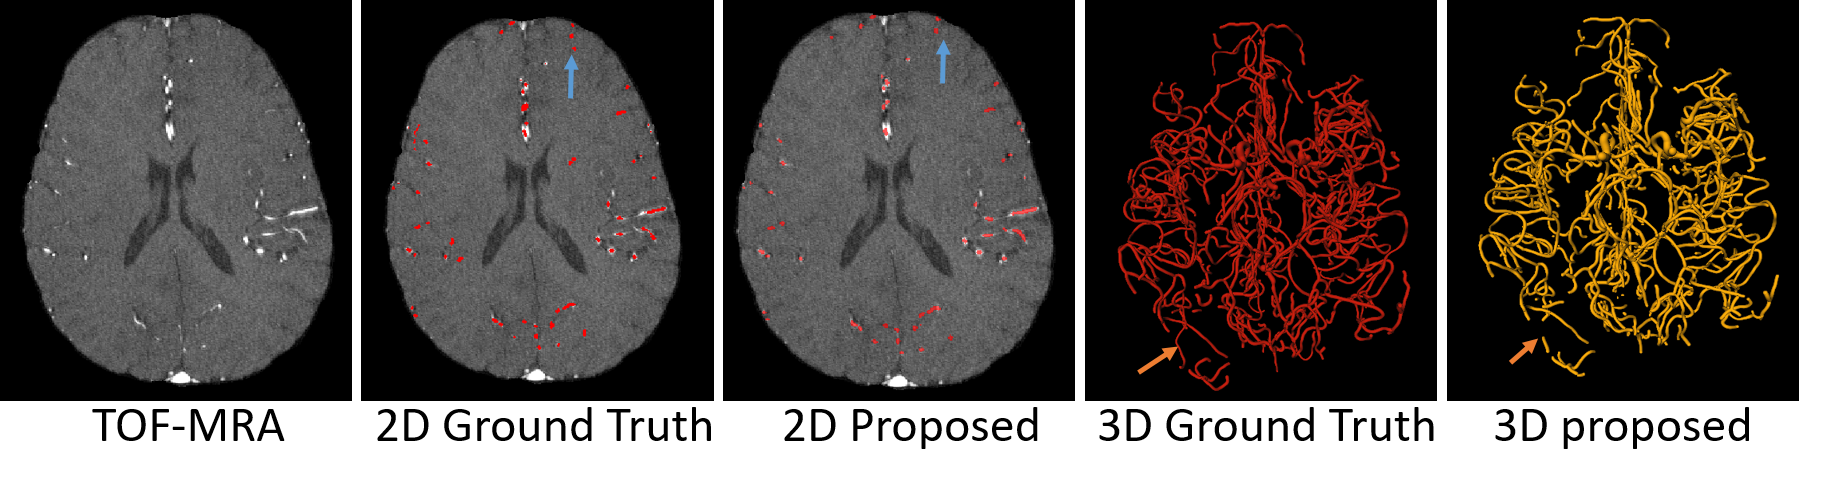

CV-AttentionUNet looks for salient regions, such as vessels, in the image and aggregates the information using deep supervision. As vessels are small and have varied sizes, we have to choose the appropriate patch size. A large patch size in multiple pooling operations may result in making small vessels invisible, and a small patch size may lead to the loss of rich contextual information. Therefore, we chose a patch volume in accordance with the limitation of computational resources. We randomly picked 190 patches from each volume and obtained 6990 patches for the TTKL dataset. Similarly, for TTKU_L, we obtained 190 patches of each image, for a total of 11216 patches for training and validation. The quantitative results of our method for TTKL and TTKU_L data are shown in Table 2. From the table, it is evident that we achieved significant improvement, with DSC scores of 70.85% and 91.74% for both labeled datasets. CV-AttentionUNet achieved remarkable results on cerebrovascular segmentation. The TTKL and TTKU_L datasets differ in terms of sensitivity, DSC score, and precision. Due to the large number of tiny vessels in the TTKL dataset, almost all of which are the size of a dot, the detection was quite low, as indicated in the sensitivity score in Table 3. Additionally, they are difficult to segment because of the nature of the data and the errors in conversion from spatial objects to NIfTI format. Similarly, the qualitative results of our method for TTKL and TTKU_L are shown in Fig. 6 and Fig.7. It is deduced from both figures that our method can learn more 3D contextual information and can extract the vessel with the help of attention and deep supervision modules. From the qualitative analysis, one can observe that TTKU_L has similar large vessels, but quite a few small vessels are missing compared to TTKL. In TTKL, some small vessels are missed by the proposed method, as shown by the blue and orange arrows (Fig. 6). Similarly, for TTKU_L, the large and missing vessels are indicated by blue and orange arrows, respectively (Fig. 7).

Particular areas of vessels for emphasis are marked with white, green, and blue arrows in Fig. 8, where 3D and 2D cross sections of the same subject are indicated by A and , respectively. Similarly, for TTKU_L, we showed two different cross sections where large vessels were marked with different colors in Fig. 9 for another subject B. It can be observed that the large vessels are correctly classified with all three comparative methods. However, false positives are present for small vessels, as shown by the orange, white, blue, and green arrows for the two subjects A and B. To draw a comparison between the ground truth and predicted result, we also presented the error maps in Figs. 8 & 9. For both TTKL and TTKU_L data, small vessels are detected better when compared with other methods, which shows that our method generalizes data well.